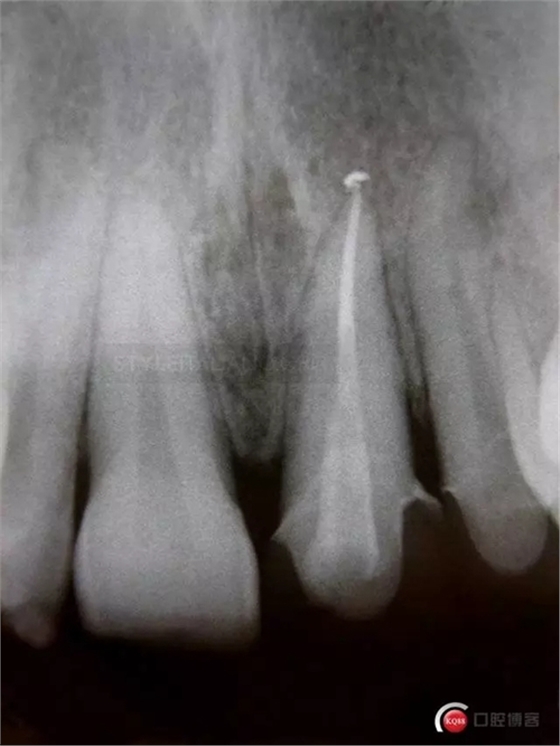

The control x-ray shows emergency profile modification on tooth 2.1 and restorations sealing even if composite overlays are quite radio transparent

4 years check

10 years check